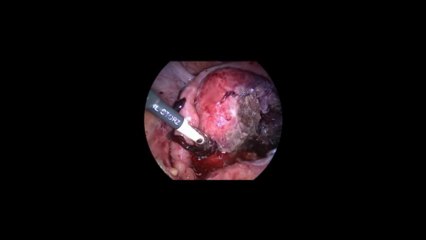

Laparoskopi ile Endometiroma 32 - Prof. Dr. Aydan Biri

Laparoskopi ile Endometiroma 32 - Prof. Dr.